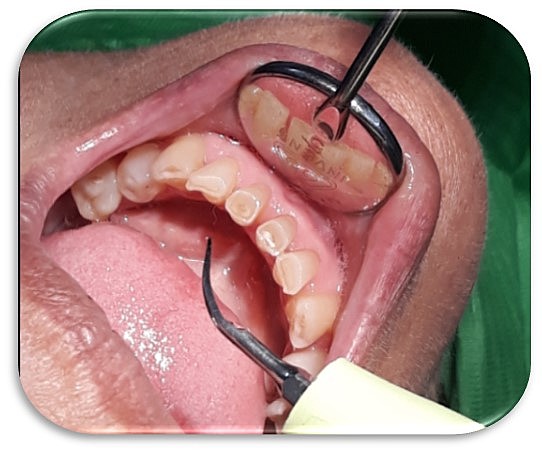

• Sondeo y periodontograma

Sondeo y periodontograma

Se observa presencia de placa sangrado. De igual manera, bolsas mayores de 3 en OD 1.7, 1.5, 2.5, 3.5, 4.4 Y 4.5.